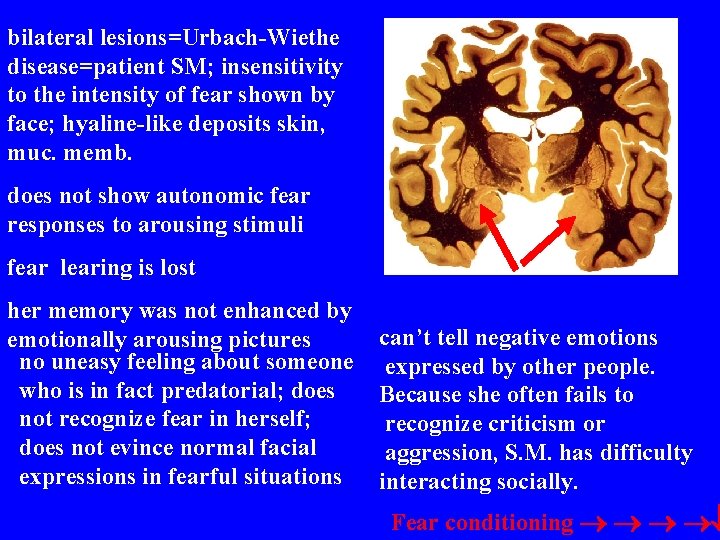

bilateral lesions=Urbach-Wiethe disease=patient SM; insensitivity to the intensity of fear shown by face; hyaline-like deposits skin, muc. memb. does not show autonomic fear responses to arousing stimuli fear learing is lost her memory was not enhanced by emotionally arousing pictures no uneasy feeling about someone who is in fact predatorial; does not recognize fear in herself; does not evince normal facial expressions in fearful situations can’t tell negative emotions expressed by other people. Because she often fails to recognize criticism or aggression, S. M. has difficulty interacting socially. Fear conditioning